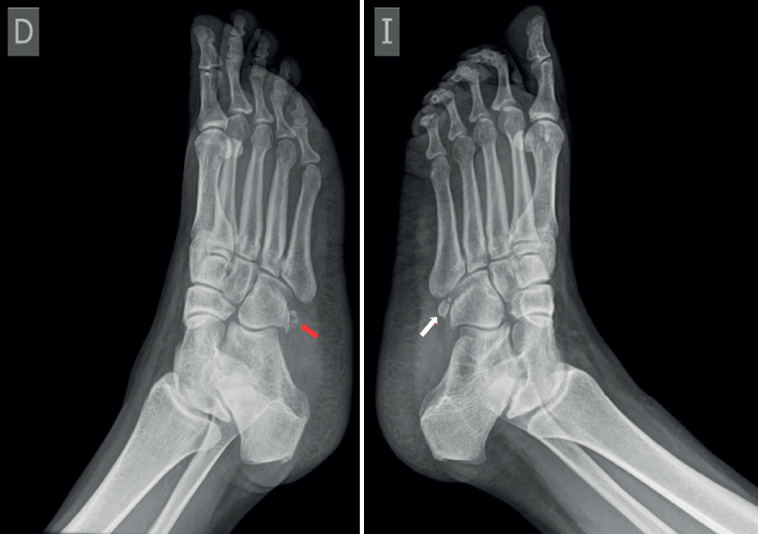

Se realizaron radiografías bilaterales del pie que evidenciaron la presencia de OP bilateral, con irregularidad en el margen del OP derecho. Inicialmente, se sospechó fractura del hueso cuboides (Figura 1); sin embargo, una tomografía computarizada (TC) descartó dicha fractura e identificó un trazo de fractura en el OP derecho, sin desplazamiento (Figura 2). Se realizó resonancia magnética (RM) del pie derecho que confirmó edema en OP del TPL, no desplazada ni complicada. TPL íntegro.

En el caso presentado se sospechó radiográficamente fractura del hueso cuboides, por lo que se indicó TC que informó fractura no desplazada de OP. El uso combinado de radiografías bilaterales (Figura 4) y TC (Figura 2) permitió diferenciar la presencia de variantes anatómicas como el OP, además de distinguir un OP bipartito de una fractura de este.